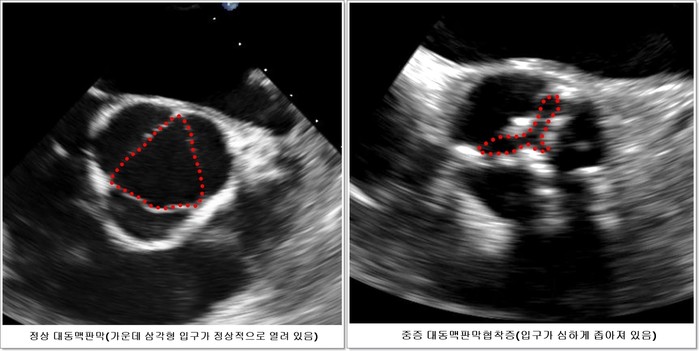

| ▲ 심장 초음파 사진(서울아산병원 제공) |

중증 대동맥판막협착증 환자의 3분의 1은 무증상으로 심장초음파 등을 통해 우연히 발견되는데, 지금까지는 심장초음파 등을 통해 무증상 대동맥판막협착증이 진단되더라도 특별한 치료 없이 주의 깊게 관찰하다가 증상이 발생하면 대동맥판막을 교체하는 수술을 받도록 권장했다. 하지만 중증이더라도 증상이 없다면 관찰을 하는 것과 증상이 없더라도 수술의 위험을 감수하고라도 수술을 하는 게 환자에게 이로운 지에 대해 명확한 기준이 없었다.